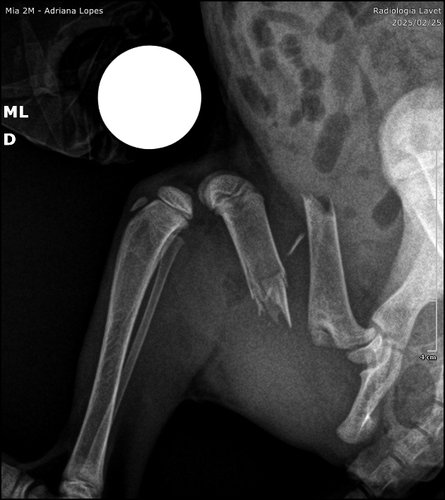

Criei essa vaquinha para ajudar a pagar a cirurgia da gatinha foi achada em uma caixa no sol no calor de 35 graus, ela está com fêmum fraturado e não sabemos como, provavelmente de maus tratos, ela não tem nem 2 meses e está lutando contra a vida e precisa dessa cirurgia o quanto antes.